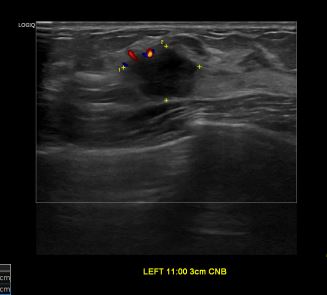

상기환자 조직검사 권유받아 내원하신 40대 여성분으로

좌측유방 혹 총조직검사 시행해 유방암 진단되었습니다.